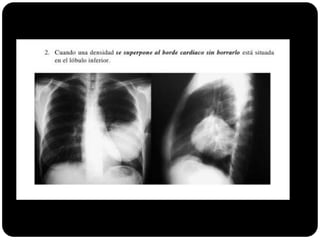

Sinal da silhueta

Lobo médio: borra o contorno direito do coração.

Língula: borra o contorno esquerdo do coração.

Segmentos basais: borram o contorno do diafragma*** (olhar

imagens anteriores para ver quais).